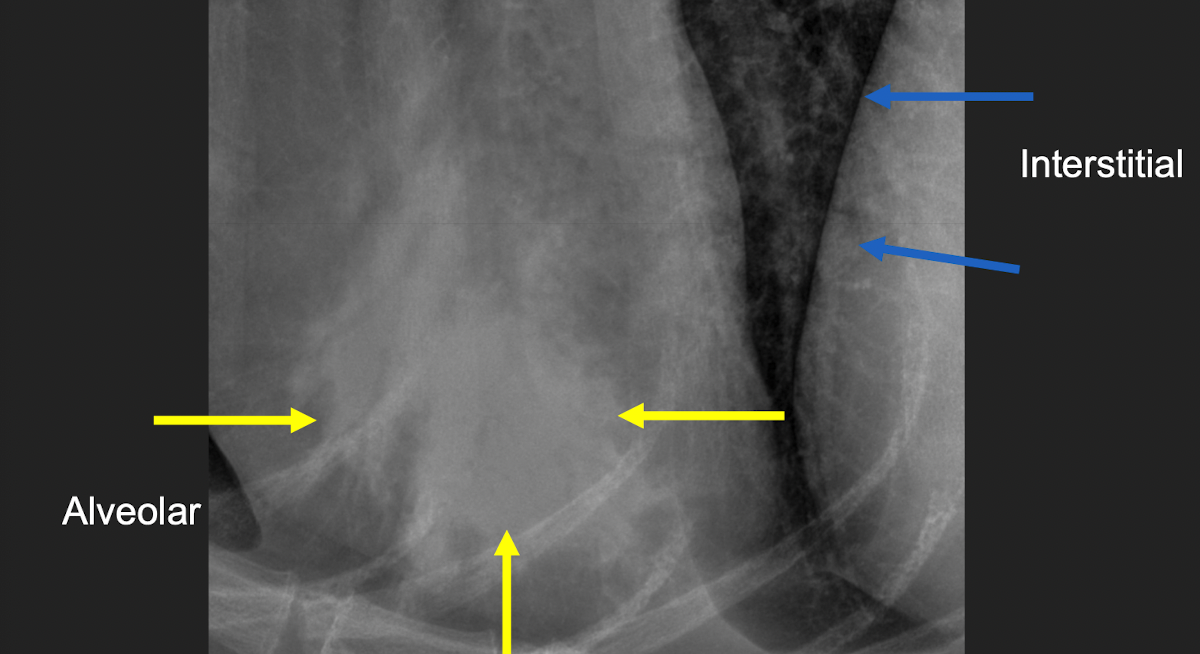

what kind of pattern

normal- left

interstitial- right